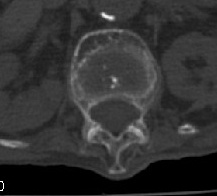

男:89岁因外伤后2天行ct检查。请各位战友讨论图中所指是否是骨折和形成该影像的原因(扫描层面位于椎体中份)。

椎体前缘双边征,其后椎体内密度增高均提示压缩性骨折

压缩性骨折,骨质疏松,前缘密度增高,考虑压缩所致

老年性骨质疏松症、压缩性骨折,退行性变。

我的报告1:腰椎骨质退行性改变。

2:t12改变考虑压缩骨折?请结合临床。